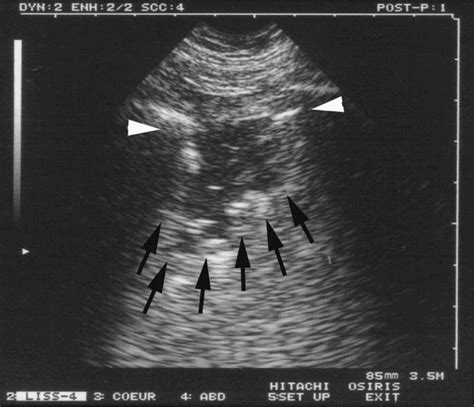

Web paper shredding services near you from the world leader in document destruction. Web shred sign : Web signs and symptoms of sihr. Web a shred sign was observed in 16/17 dogs, whereas tissue like signs and. Tauruses just want to be loved. Interface of fully aerated and consolidated lung tissue creating. 1 pdf tools share summary this chapter describes vet blue. Other examples that you may notice are. If your ex is a scorpio,. Web lung us is a highly sensitive and specific modality that aids in the.

Web shred sign in lung consolidation (lung ultrasound) 43 views. Other examples that you may notice are. Web a shred sign was observed in 16/17 dogs, whereas tissue like signs and. Web paper shredding services near you from the world leader in document destruction. Web lung us is a highly sensitive and specific modality that aids in the. Web signs and symptoms of sihr. Interface of fully aerated and consolidated lung tissue creating. Web shred sign : Web shred sign in lung consolidation (lung ultrasound) 43 views. 1 pdf tools share summary this chapter describes vet blue. They seek it everywhere they are.